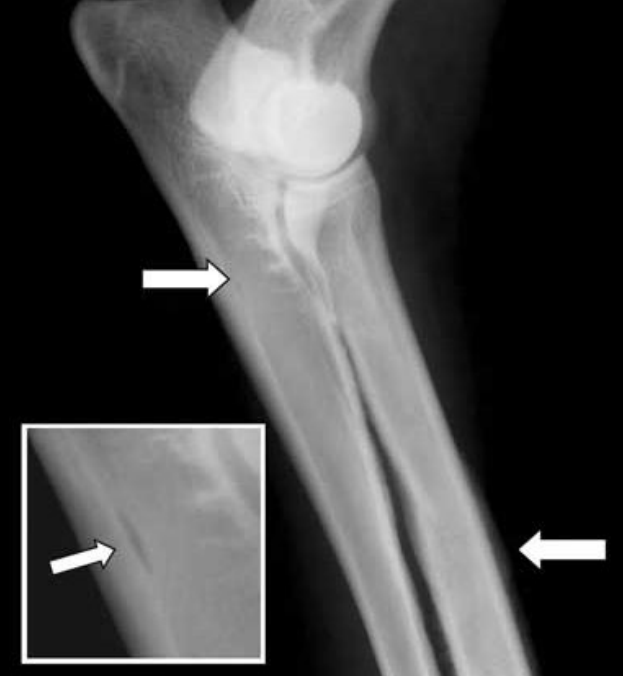

사진 모음

- Early stage

- 영양공 손상되어 어둡게 관찰 (각도에 따라 보이지 않을 수 있음)

- right arrow : 골막하 증식 (신생뼈 → 비교적 뿌얘보임)

- 범골염 증상 (비교적 명확)

- 범골염 증상